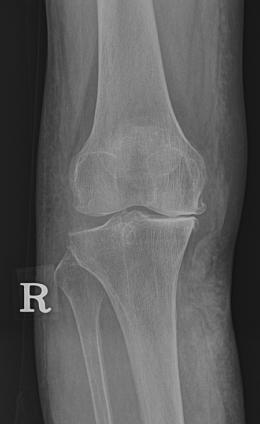

정상적인 모습

환자의 모습